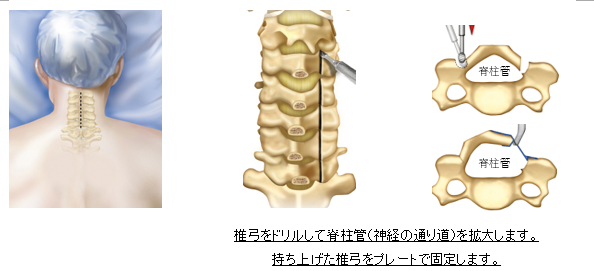

頸椎椎弓形成術(Cervical Laminoplasty:CLAP)

適応:頚椎症性脊髄症、頚椎椎間板ヘルニア

頚椎症や頚椎椎間板ヘルニアによる脊髄症に対する方法です。長期成績が安定しており、

多椎間に病態がある患者さんに適した治療法です。術後10-14日程度で退院可能です。